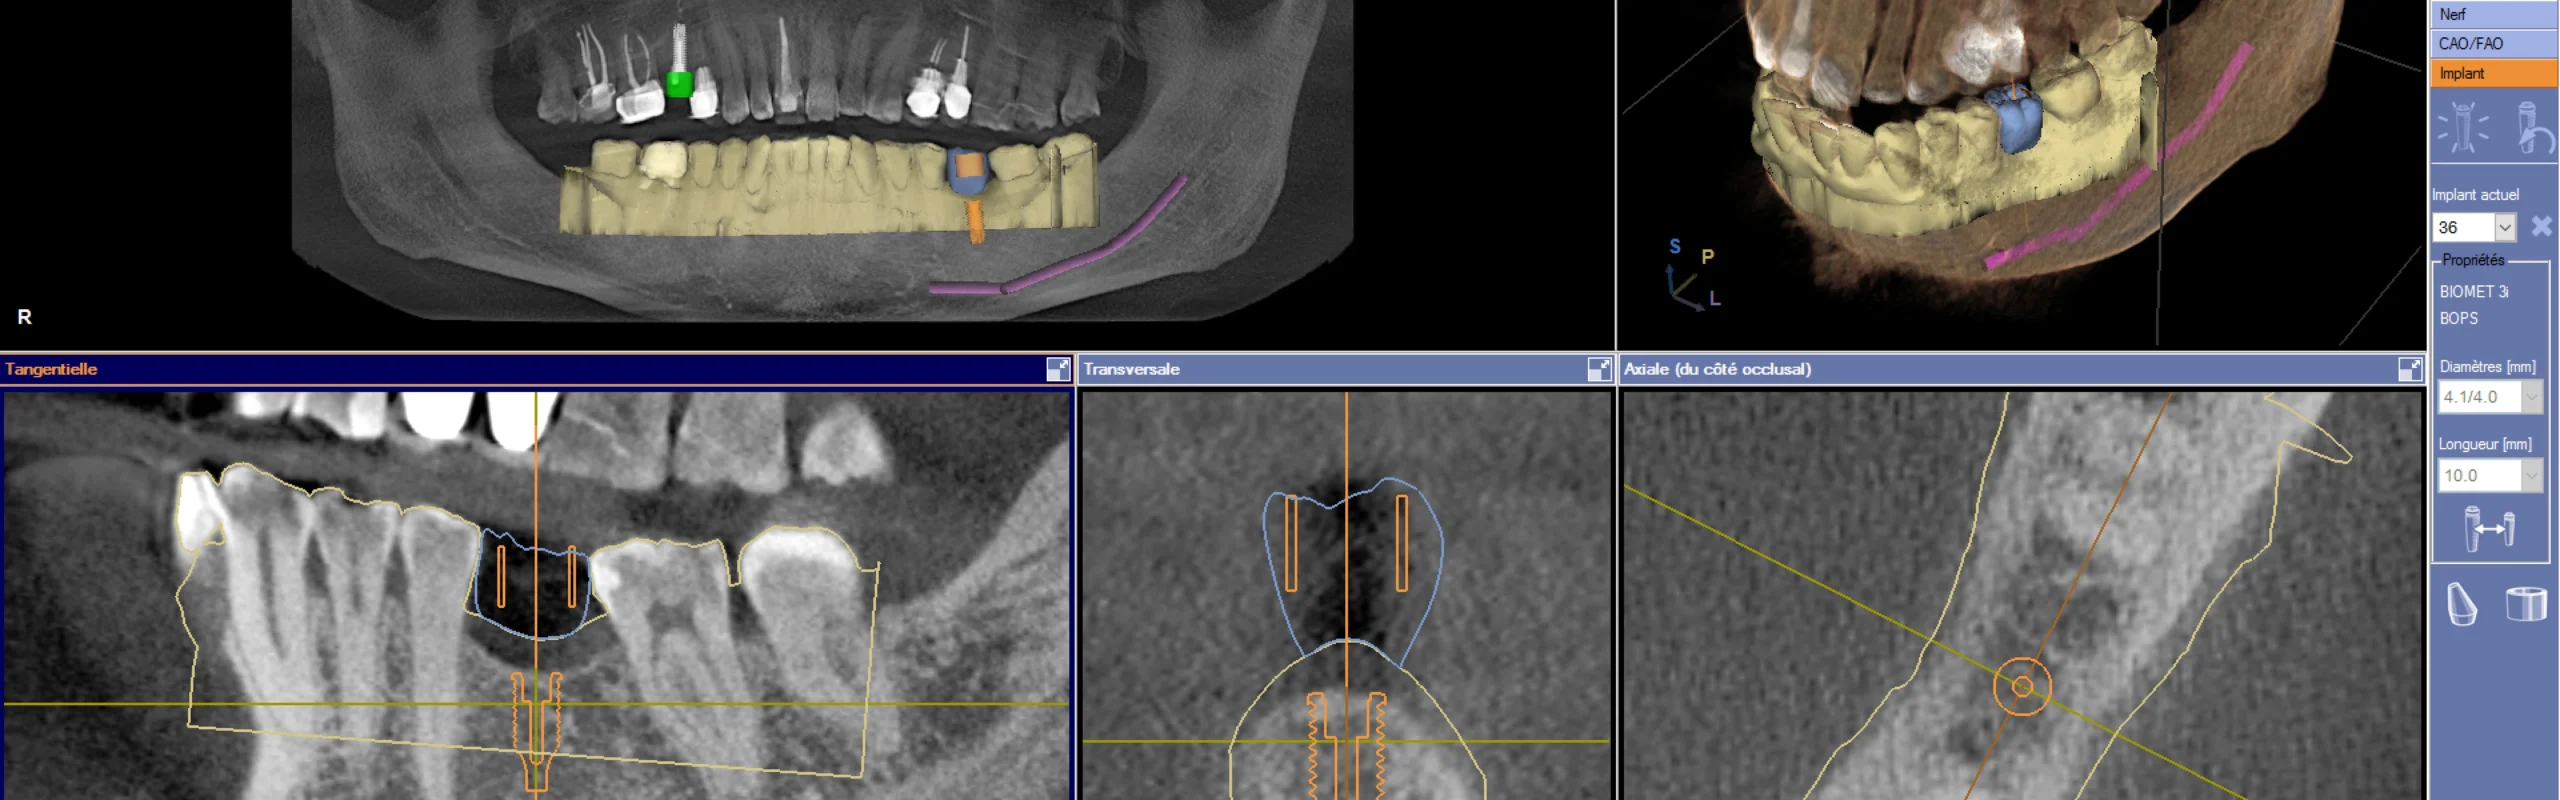

Planification sur ordinateur

Grâce à des logiciels performants, il est possible de simuler avec une grande précision le positionnement de l’implant en 3D. Cette approche prend en compte la future prothèse ainsi que les structures anatomiques environnantes, garantissant une intégration optimale et sécurisée.

L’implantation précise dans l’os repose sur l’utilisation de guides chirurgicaux, qu’ils soient statiques ou dynamiques. Ces dispositifs permettent d’assurer un positionnement tridimensionnel optimal lors de l’intervention.